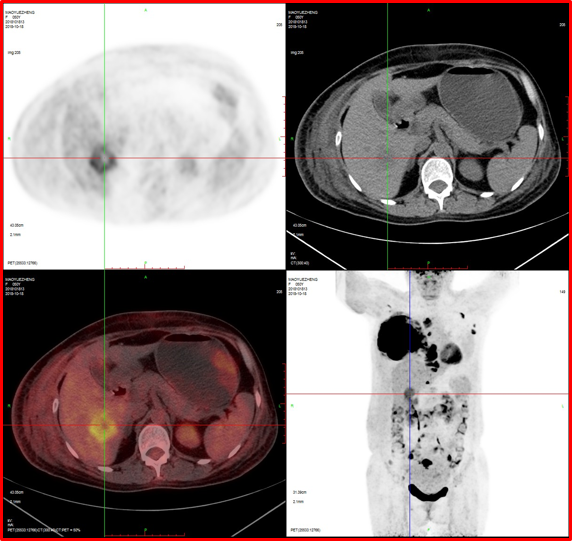

病例1:女性,50歲,乳腺腫瘤術(shù)前評估。

PET/CT檢查:

1、右側(cè)乳腺惡性腫瘤;

2、肝臟轉(zhuǎn)移。